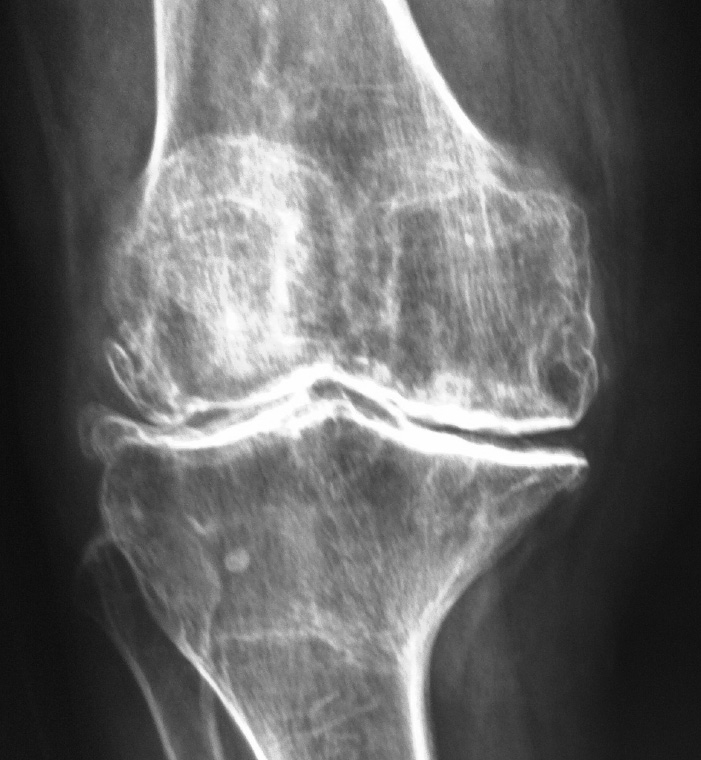

Sin embargo, el desgaste por lesiones del cartílago traumáticas, por envejecimiento (osteoartritis), por secuelas de fracturas o traumatismos, una mala alineación de la articulación o no resueltas en tiempo y forma, alteran dicha armonía en la función articular provocando de manera progresiva dolor, rigidez articular, debilidad muscular y disminución de la función.

La principal causa del dolor crónico de la rodilla que condiciona discapacidad por desgaste articular es la osteoartrosis, sin embargo, la artritis reumatoide y el desgaste articular postraumático, son causas frecuentes de lesión del cartílago de manera extensa y acelerada.

• La osteoartrosis es un tipo de enfermedad articular por uso, envejecimiento y desgaste relacionado con la edad. Habitualmente se presenta en personas mayores de 50 años.

• La artritis reumatoide es una enfermedad sistémica que se caracteriza por inflamación crónica de las articulaciones, provocando que la membrana que las envuelve se engruese.

• Habitualmente la inflamación crónica y el engrosamiento de los tejidos dañan al cartílago articular. El desenlace final es dolor, deformidad y rigidez de la articulación

• El desgaste articular pos-traumático se presenta después de una lesión seria de la rodilla, en específico, fracturas del hueso y cartílago que conforman la articulación y lesiones de los ligamentos que estabilizan la articulación no resueltas o crónicas.